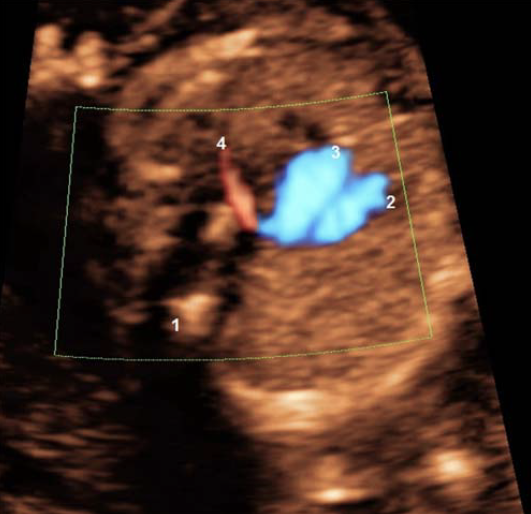

הדמיית ההריון והתפתחותו

הרצאתו של פרופסור רון בלוססקי מיחידת האולטרא סאונד והיחידה להריון בסיכון גבוה במחלקת נשים ויולדות בקריה הרפואית...